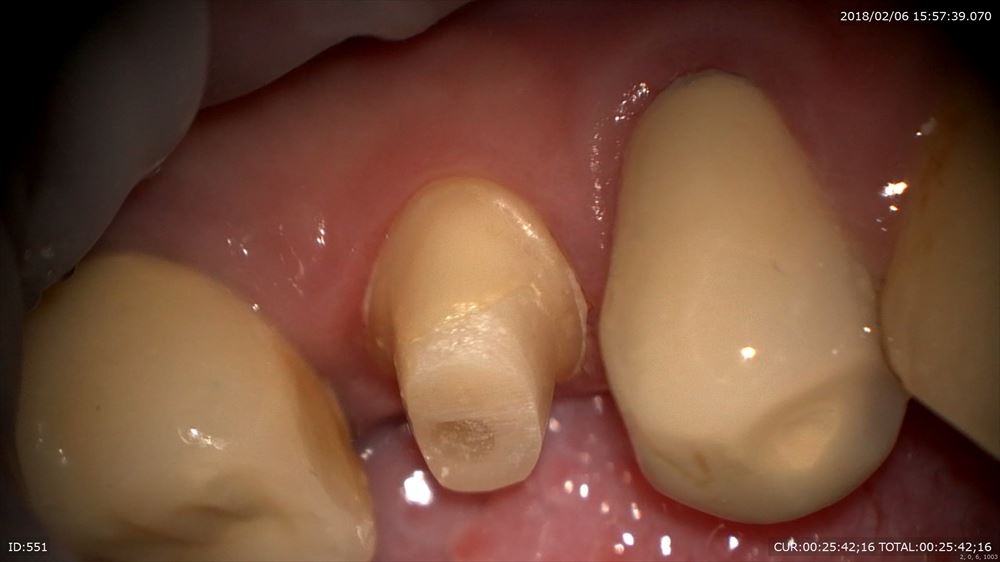

次のケースはハイブリットのセット

これは仮歯。仮歯入れない事はありません。歯茎の為。かみ合わせの為必須。

仮歯を外して

セット。喜んで頂けました。元々この方は中等度の歯周病でした。とても真面目に治療に参加して頂き歯周病の再発はありません。本当に感謝。次回PMTC!